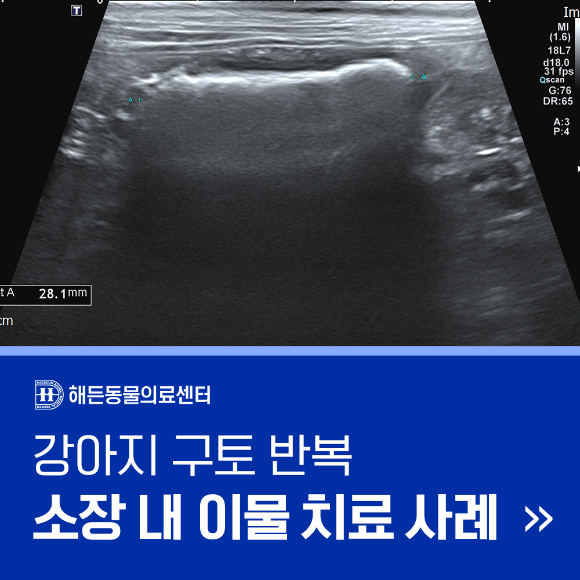

이번 사례는 강아지가 반복적인 구토 증상을 보여 내원하여

초음파 검사 결과 소장 내 이물이 확인되었고,

내과적 치료와 약물 처방을 통해 증상이 호전된 과정을 담고 있습니다.